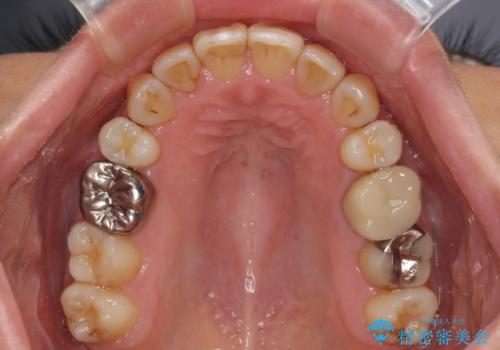

舌のトレーニングをしっかりと行ってくださり、10ヶ月で希望通りの歯列となりました。

日頃から飲まれる飲み物の影響で着色しやすいため、来院の度に着色除去のクリーニングも行っていました。